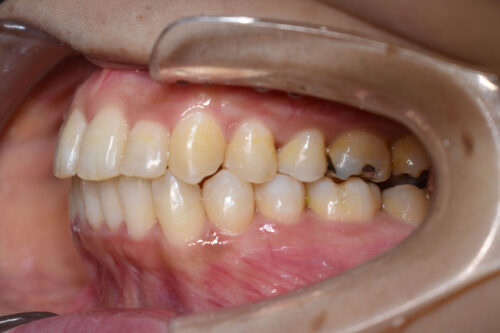

初診時年齢 39歳 女性

歯のでこぼこ(叢生)

を主訴に

池袋よりひとつ隣駅の東京都豊島区大塚駅すぐの大塚たまみ矯正歯科へ

いらっしゃいました。

奥歯のかみ合わせに 前後的な ずれは ないものの

上下ともに 前歯部に

顕著な 叢生(でこぼこ)が

認められました。